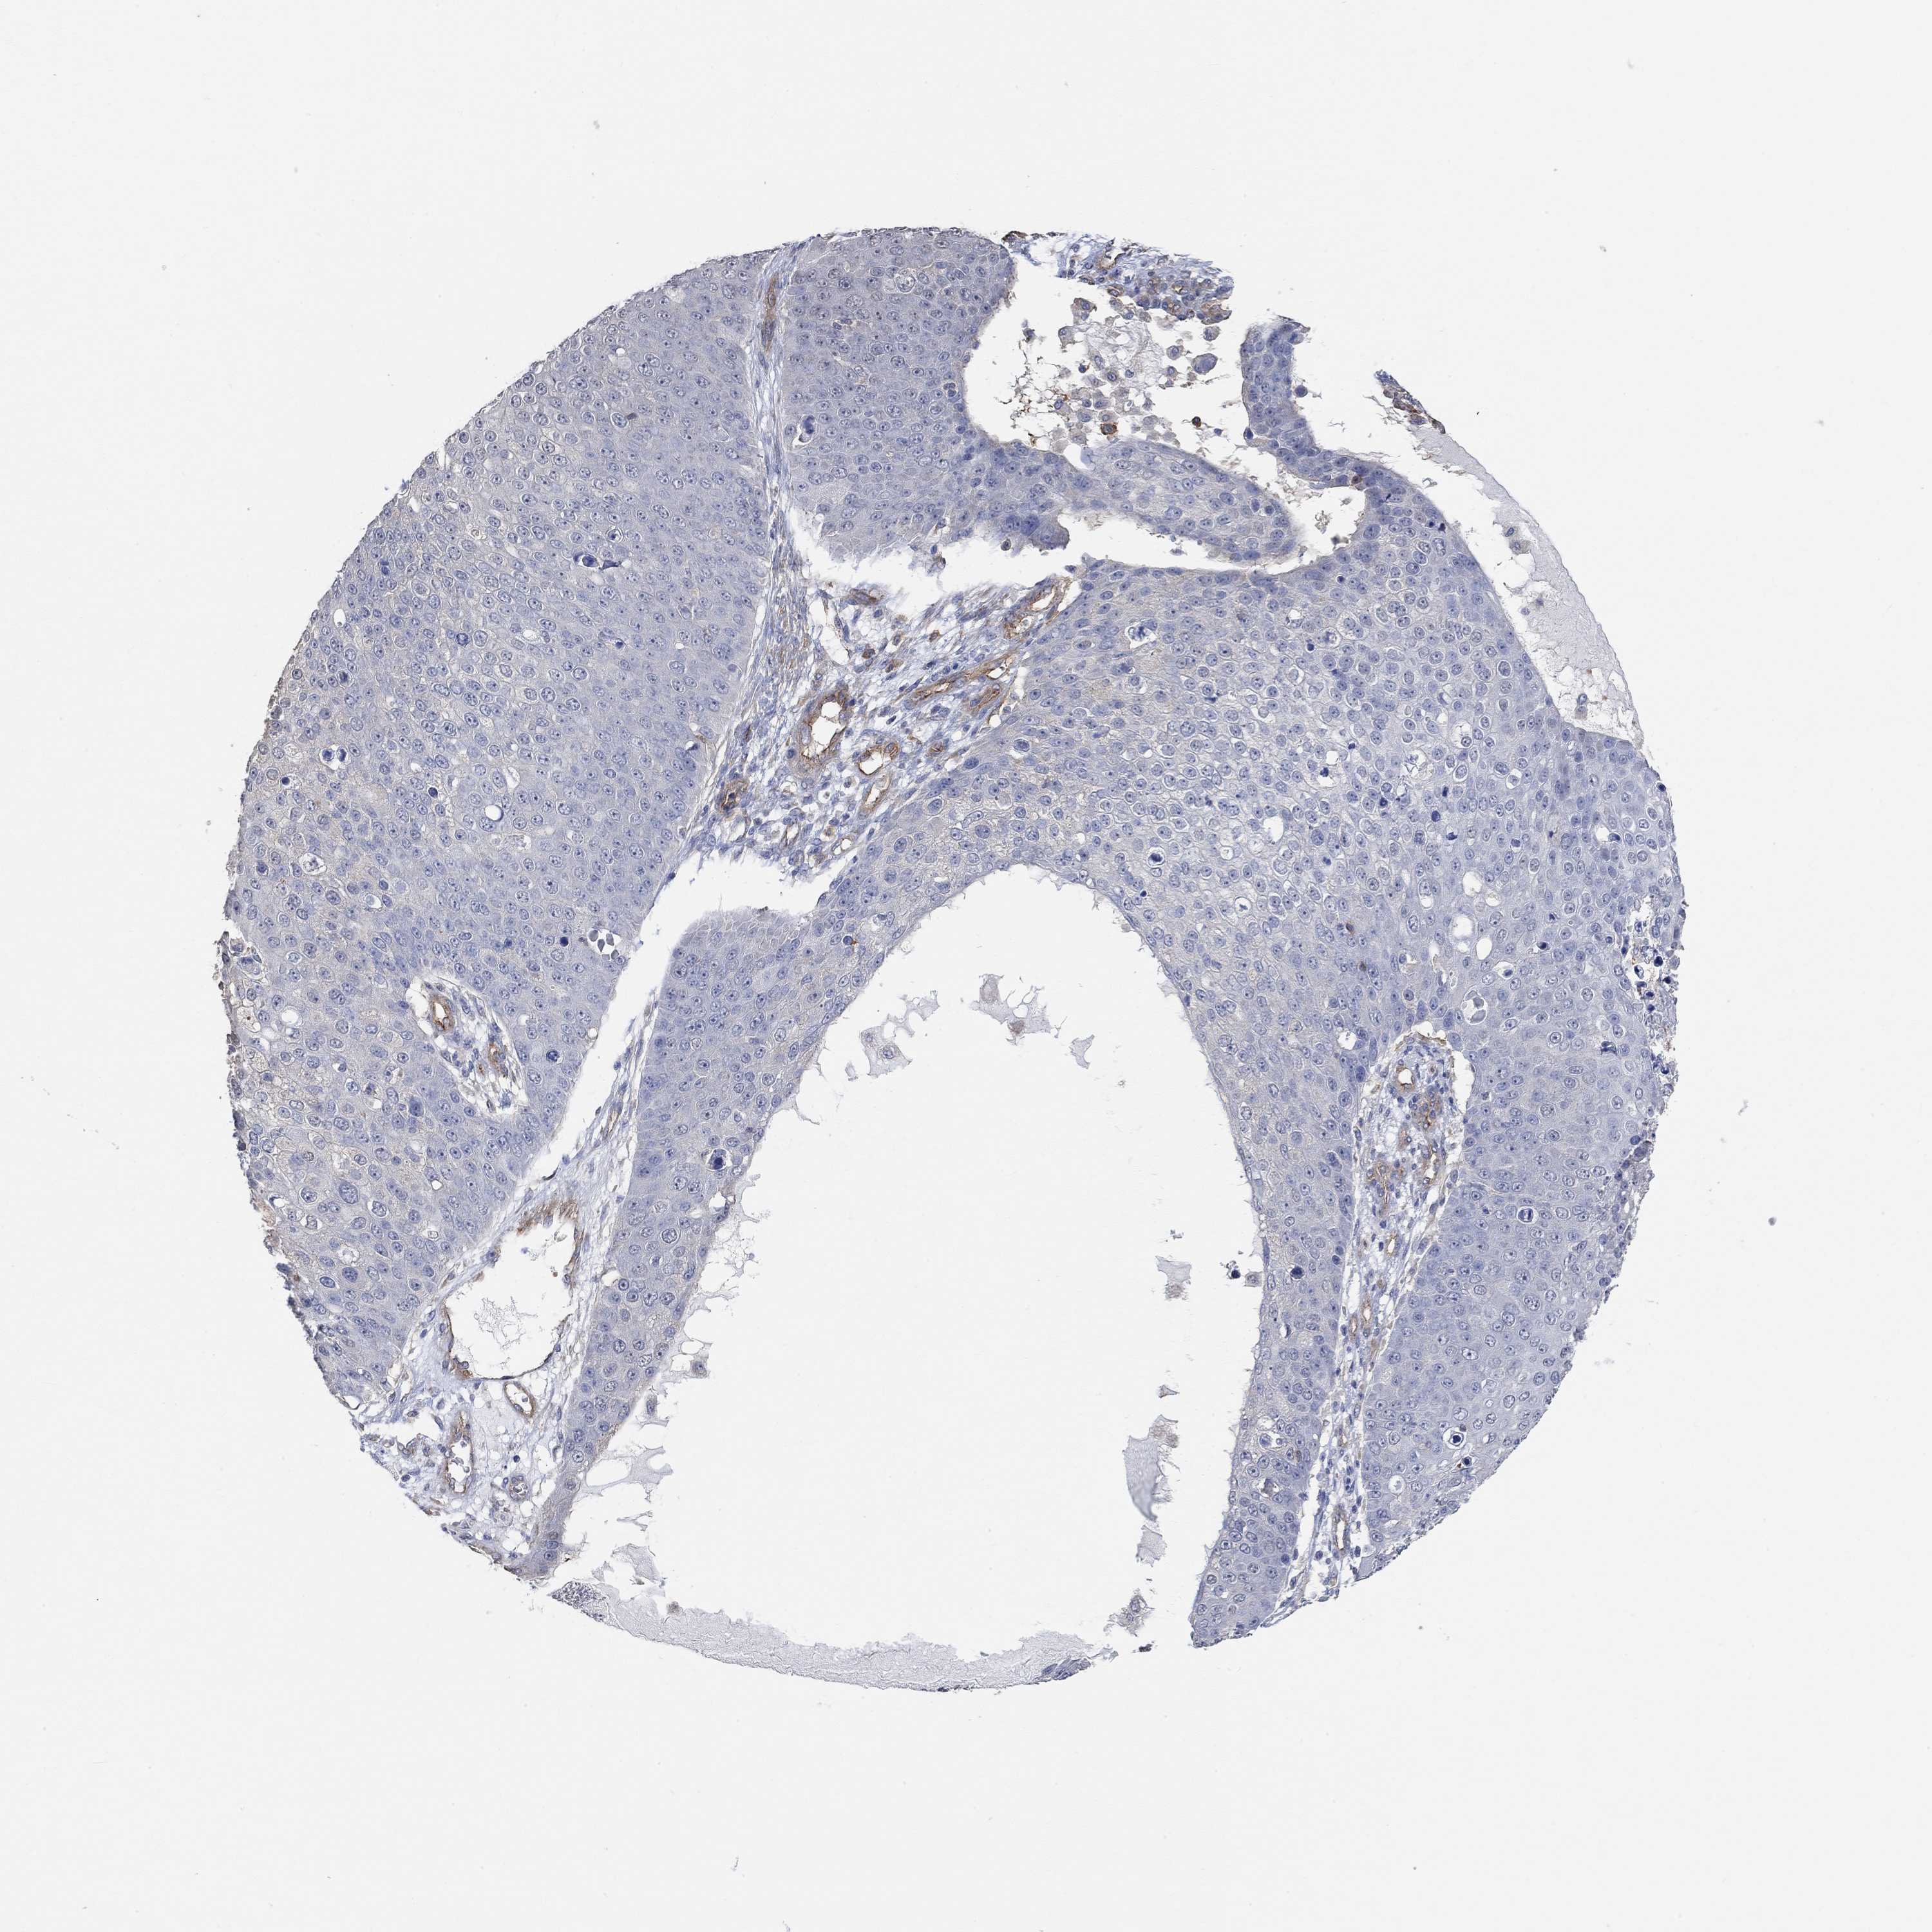

Basal cell and squamous cell cancer

SKIN CANCER - Protein expressioni

A mouse-over function shows sample information and annotation data. Click on an image to view it in a full screen mode. Samples can be filtered based on level of antibody staining by selecting one or several of the following categories: high, medium, low and not detected. The assay and annotation is described here.

Antibody stainingi

Antibody staining in the annotated cell types in the current human tissue is reported as not detected, low, medium, or high, based on conventional immunohistochemistry profiling in selected tissues. This score is based on the combination of the staining intensity and fraction of stained cells.

Each image is clickable and will lead to virtual microscopy that enables deeper exploration of all samples and also displays staining intensity scores, fraction scores and subcellular localization as well as patient and tissue information for each sample.

Antibody HPA004199

Squamous cell carcinoma, NOS

Basal cell carcinoma